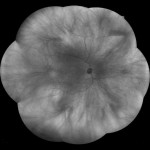

超広角視野画像

最大200°の超広角視野

Eidon独自のシャープネスと、TrueColorの組み合わせにより、網膜撮影画角が1回のショットで120°撮影が可能です。

モザイク機能を使用することで最大200°まで広角になり、周辺部の微細な病状を検出するのに役立ちます。